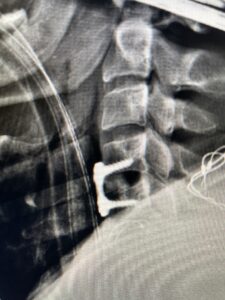

This 47-year-old male who four months prior was lifting weights developed sharp pain in his neck. After that he developed progressive numbness in his arms, neck pain and headache. He said that the right arm was worse than the left. On examination the patient had long tract weakness on the right side which included his triceps, finger extensors, hip flexors, and dorsiflexors. The patient did not have hyperreflexia. MRI (Fig. 2) demonstrated a massive, extruded disc herniation with severe cord compression. The patient because of progressive myelopathy and spinal cord compression was indicated for anterior cervical discectomy and fusion at C4-5 (Fig. 3). Patient had significant improvement of weakness and numbness post operatively.

Fig. 2a Sagittal T2-weighted cervical MRI demonstrating large C4-5 herniated disc with spinal cord compression (red arrow)

Fig: 2b Axial T2-weighted cervical MRI demonstrating spinal cord compression from C4-5 herniated disc (red arrow)